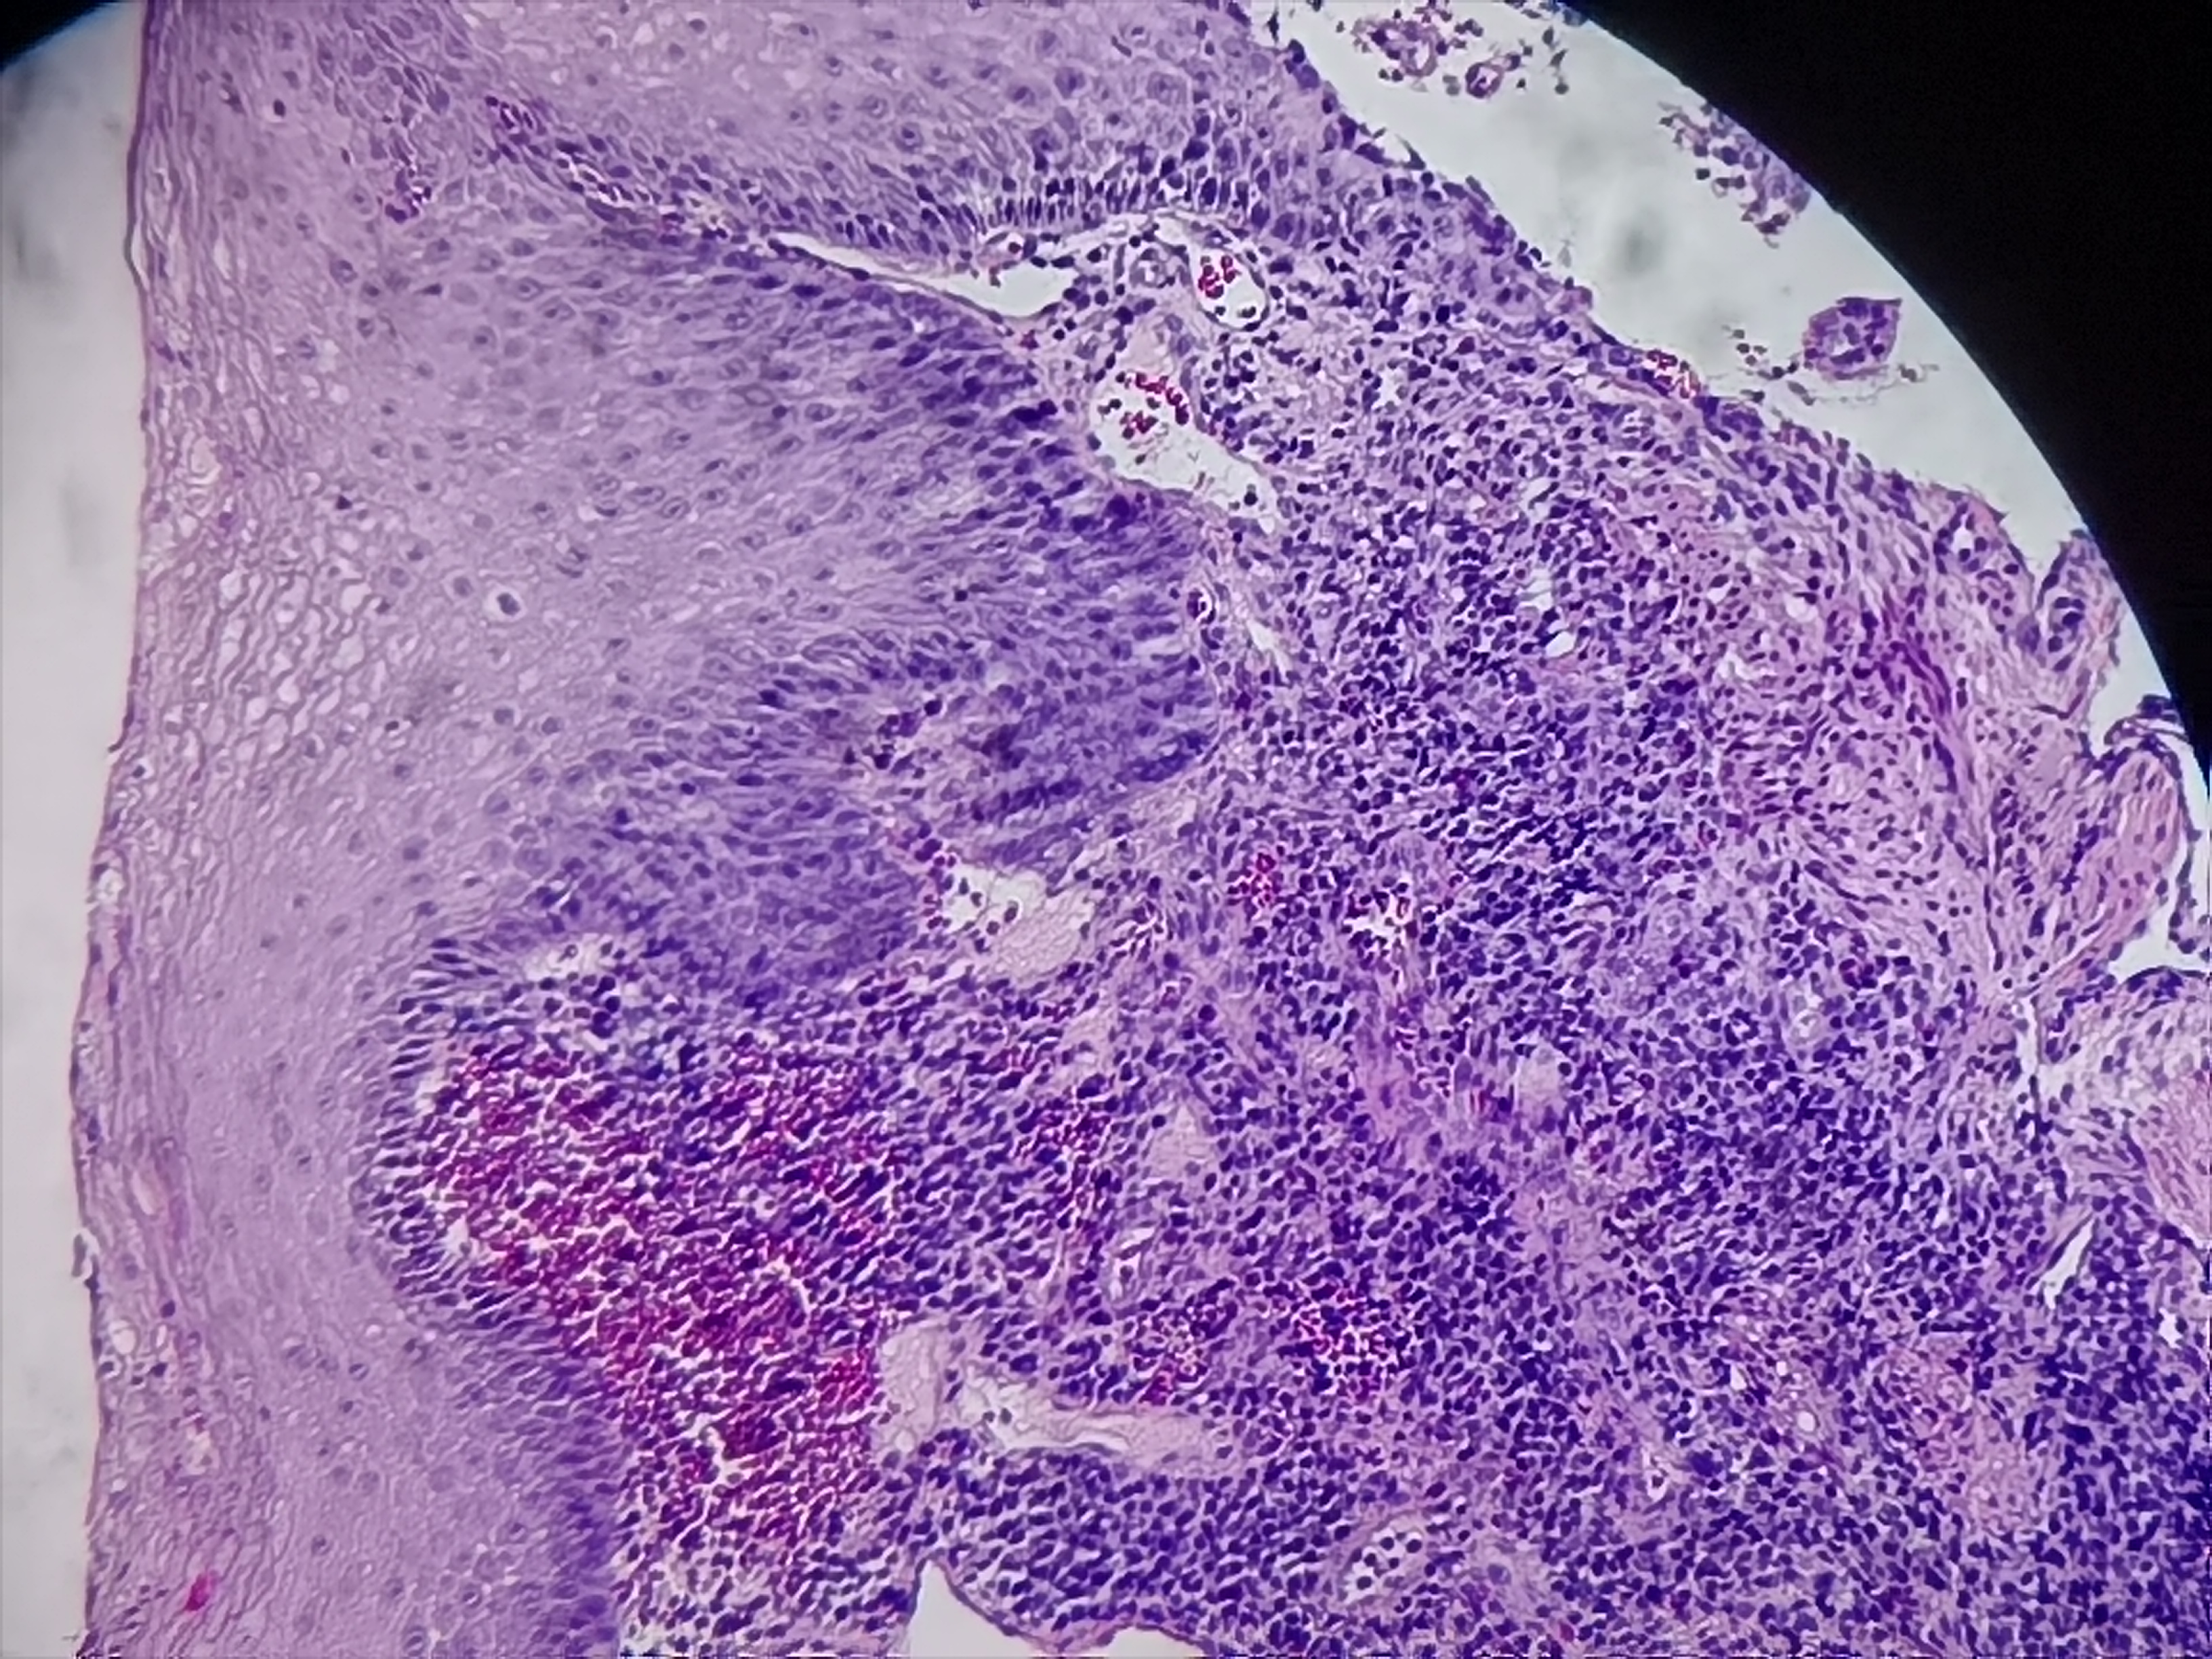

食管活检

性别

男

年龄

60岁

食管:距门齿21-27cm处可见不规则病灶

食管粘膜活检

灰白色组织4块

请教各位老师

图2

SCC..